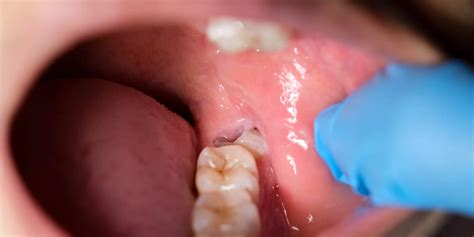

Experiencing sudden, throbbing pain in the back of your mouth is often the first sign that something is wrong with your third molars. A wisdom tooth abscess is a serious dental condition that occurs when a pocket of pus forms due to a bacterial infection in or around the wisdom tooth. Because these teeth are the last to emerge, they often lack the space to grow in properly, leading to impaction or partial eruption. When this happens, a flap of gum tissue—known as an operculum—can trap food debris and bacteria, creating the perfect environment for an infection to thrive.

• Pericoronitis: This is an inflammation of the gum flap surrounding a partially erupted tooth.

• Swelling: You may notice red, inflamed gums around the wisdom tooth or visible swelling on the side of your face or cheek.